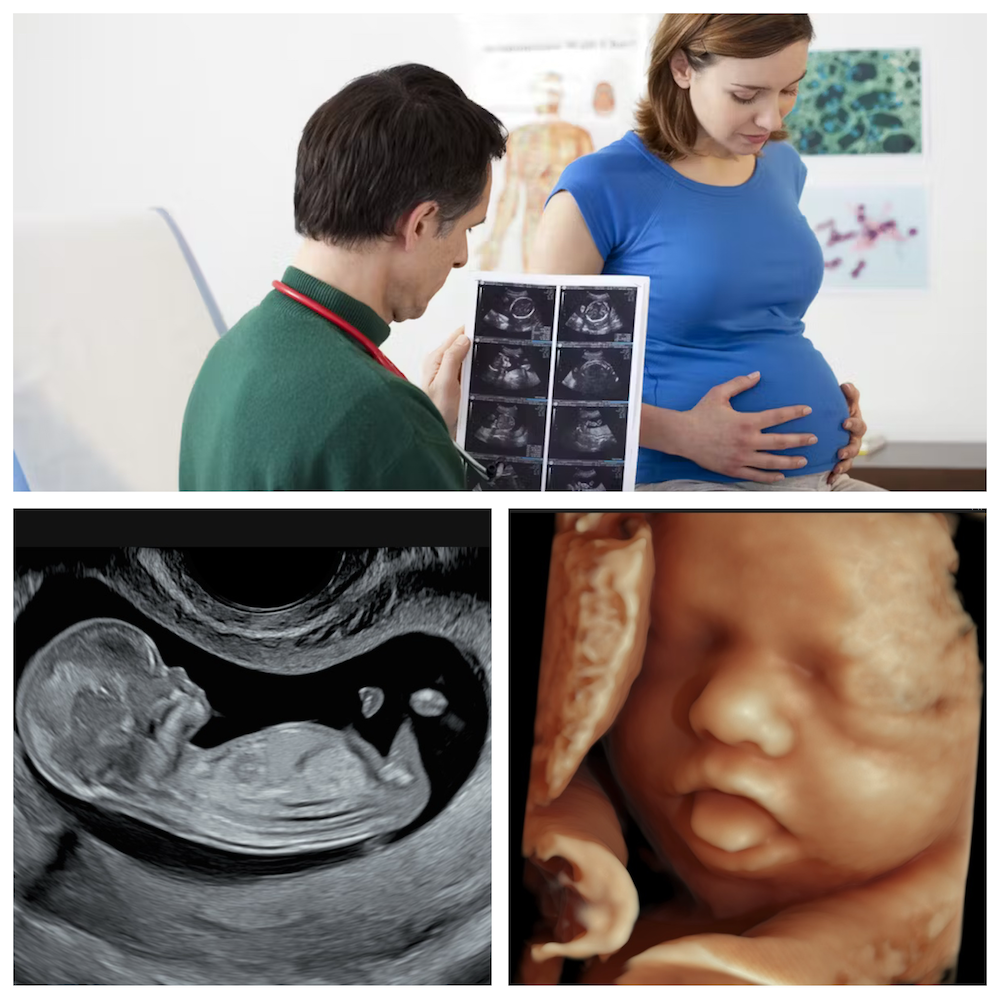

3D/4D ultrahang

11-13 hetes genetikai ultrahang

- 11.hét 0.nap - 13.hét 6.nap között, ekkor a CRL 45-84 mm között változik

- korai Down-kór szűrés FMF irányelvek szerint

18 hetes genetikai ultrahang

- a magzat anatómiájának és fejlődésének ellenőrzése

32 hetes nyomonkövető vizsgálat

- a magzat fejlődésének ellenőrzése, a vese anatómiájának ellenőrzése

36 hetes ultrahang

- a magzat súlybecslése

- a magzat fekvésének meghatározása